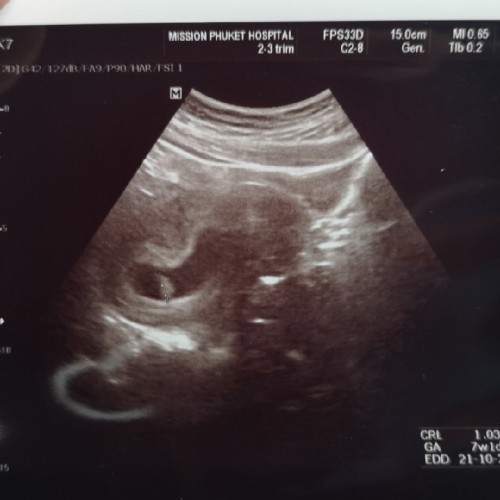

ซาวด์ตอน8w4dคะตอนแรกๆไปไม่เห็นน้อง ใจเย็นๆนะคะรอก่อนคะ ท้องสองหน้าท้องหนาคุณหมอบอกให้ทำใจคะ55 ไม่ชัดเหมือนท้องสาว ภาพนี้ซาวด์ผ่านช่องคลอดคะ